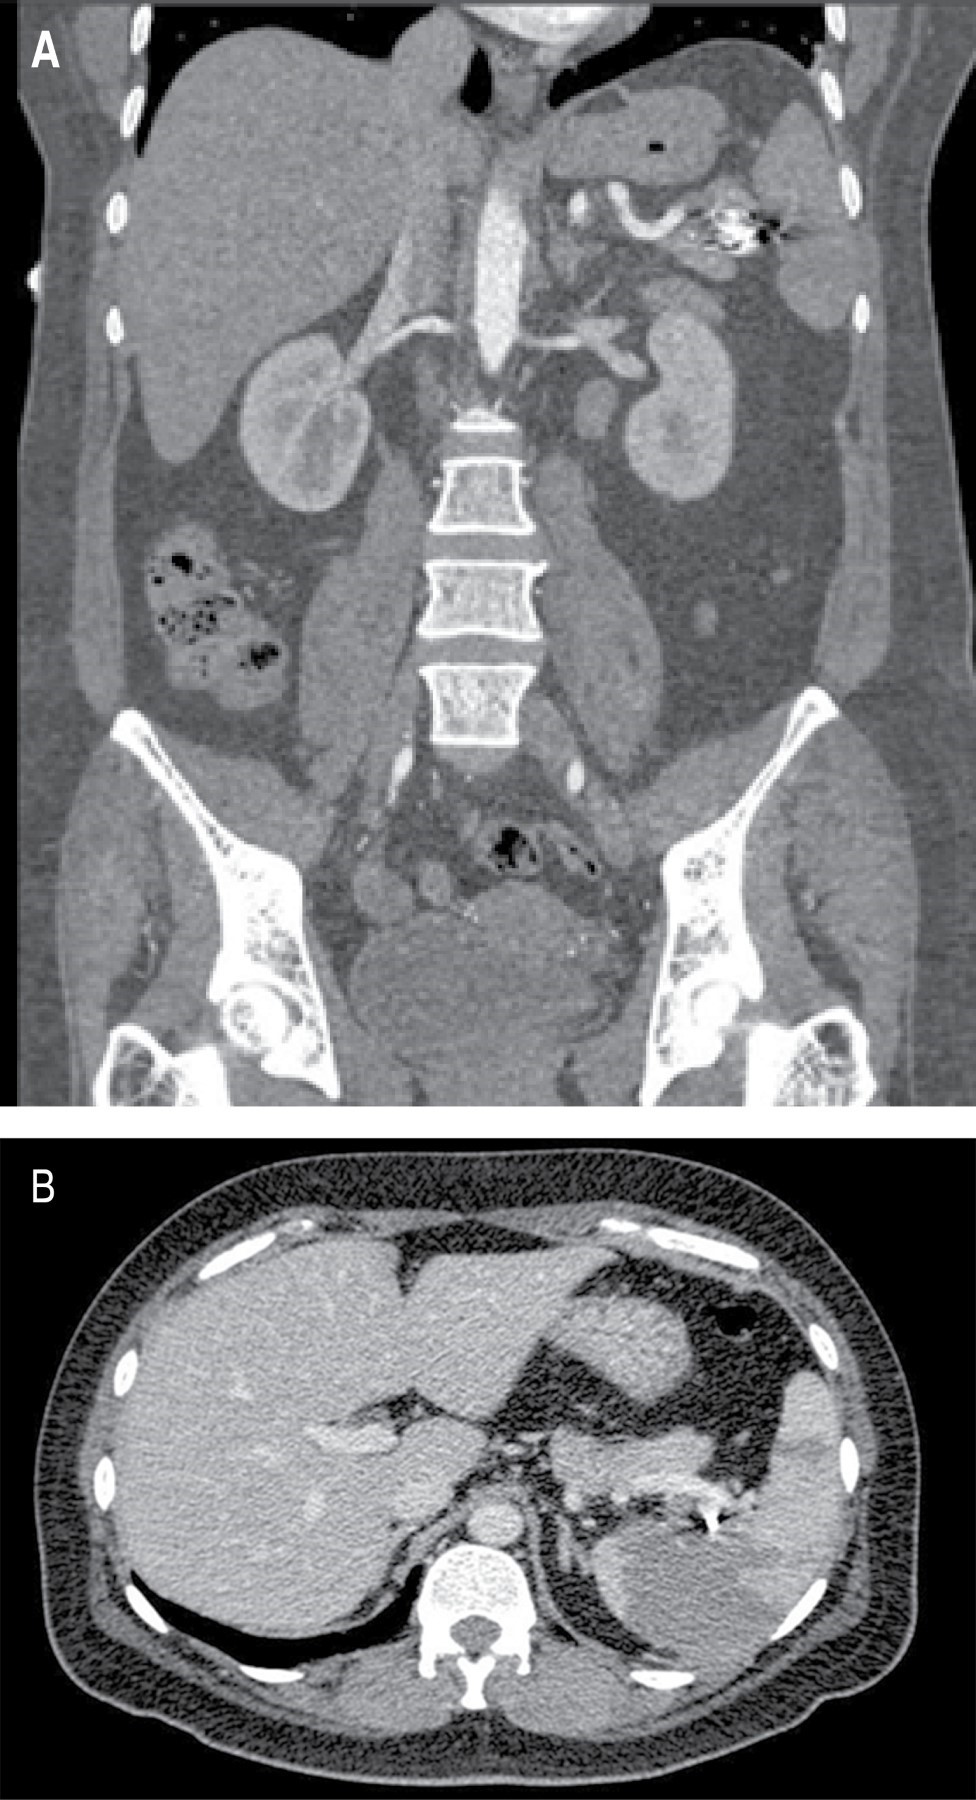

Femenino de 41 años, con antecedente de hipotiroidismo diagnosticado a los 21 años, actualmente sin tratamiento médico desde los 40 años por aparente control, diagnóstico de miomatosis uterina a los 40 años, sin tratamiento; antecedente de dos cesáreas, última a los 23 años, sin complicaciones. Accidente automovilístico con volcadura a los 40 años, sin daño orgánico aparente. Inicia padecimiento actual posterior a accidente automovilístico ocurrido un año previo con dolor en hipocondrio izquierdo, de tipo intermitente, punzante, sin irradiaciones, sin agravantes ni atenuantes; a la exploración física presenta dolor en hipocondrio izquierdo a la palpación profunda, resto sin datos patológicos. Se realizó ultrasonido con hallazgos compatibles con aneurisma de la arteria esplénica y colelitiasis, se complementa abordaje diagnóstico con angiotomografía de aorta abdominal encontrando arteria esplénica de calibre normal, con dilatación focal sacular en segmento distal compatible con aneurisma de 17.7 × 15.9 mm y cuello de 5.5 mm, con trombo mural de 2 mm, sin signos de ruptura, litiasis vesicular y miomatosis uterina. En manejo conjunto con angiología se realiza embolización selectiva con colocación de coils, sin complicaciones aparentes (Figura 1). En el seguimiento inmediato, la paciente presenta dolor abdominal y leucocitosis, se realiza nueva angiotomografía con datos sugestivos de oclusión de arteria esplénica e infarto esplénico (Figura 2). Por los hallazgos comentados se decide realizar esplenectomía y colecistectomía convencional mediante abordaje quirúrgico con incisión en línea media, supraumbilical, con los siguientes hallazgos: vesícula biliar de paredes delgadas, múltiples litos en su interior de 5-10 mm aproximadamente, arteria cística de 2 mm, conducto cístico de 3 mm, bazo de 13 × 10 cm aproximadamente, con múltiples zonas isquémicas, aneurisma de la arteria esplénica a nivel de hilio esplénico, posterior a su bifurcación (Figura 3). Cursa el postoperatorio sin complicaciones, por lo que fue egresada tres días después de la cirugía, recibió vacunación correspondiente para pacientes esplenectomizados. Reporte histopatológico con hallazgos de aneurisma de arteria esplénica con ateroesclerosis, parénquima esplénico con vasos congestivos y colecistitis crónica litiásica.

Figura 2